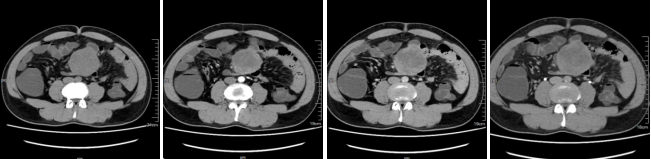

病例二 男,52歲, 以“ 下腹部包塊3天” 門診就診。 查體: 臍周可觸及包塊, 無(wú)壓痛。術(shù)后病理結(jié)果: 腸系膜內(nèi)胃腸道外的GIST, 高分化。

平掃期 動(dòng)脈期 門脈期 延遲期

該檢查使用最新的AIDR-3D迭代重建技術(shù),最大程度的降低了掃描的輻射劑量,并且能夠得到高清的圖像質(zhì)量。此病人術(shù)前4期檢查加上術(shù)后復(fù)查多次掃描總劑量?jī)H5mSV左右,目前,此技術(shù)可以用在全身各部位的檢查。